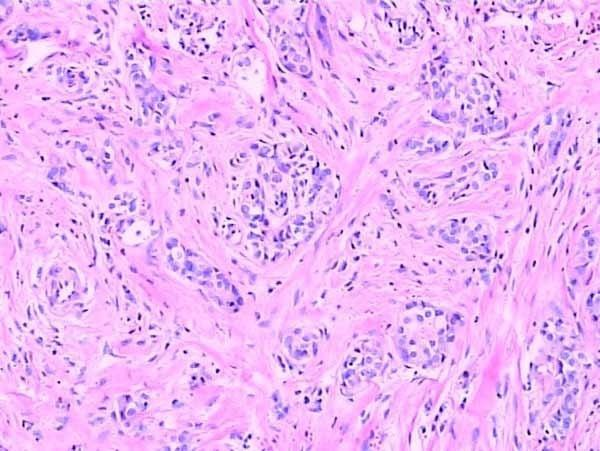

石蠟切片

此外,在染色性能方面,兩種切片技術也各有千秋。石蠟切片適用于多種染色技術,如H&E染色等,能夠清晰地展示組織的細胞結構和形態。而冰凍切片則更多地應用于免疫組化和原位雜交等特殊染色技術,為科研人員提供了更多維度的觀察手段。